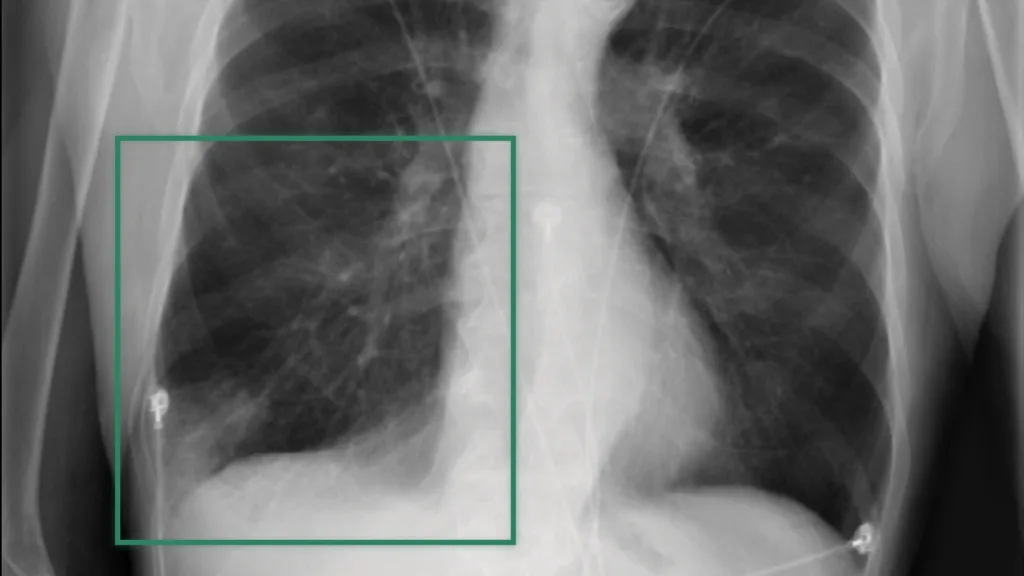

本文详细介绍了 Clara NV-Reason-CXR-3B 的技术实现,这是一款拥有 30 亿参数的视觉语言模型(VLM),专为胸部 X 光分析设计。文章阐述了数据集的构建方法——通过语音记录捕捉放射科医生的诊断思维过程,介绍了结合监督微调与基于梯度的强化学习策略的两阶段训练流程,并展示了在临床机构中进行的验证结果。

NVIDIA 研究人员利用 Clara NV-Reason-CXR-3B 模型为 Clara Reason 提供推理能力。该模型是一种专用于胸部 X 光分析的视觉语言模型(VLM),能够像放射科医生一样分析胸部 X 光片,并生成模拟医生临床思维过程的完整推理链。

THINK: We'll begin with the quality assessment of this AP chest x-ray. As you can see, the lung fields are relatively well visualized, although the patient's position and the fact that it's a portable AP view may limit the evaluation to some extent. I think the quality is acceptable for this type of examination.

Now, we are looking at the medical devices and instrumentation. I don't see any medical devices such as central venous catheters, endotracheal tubes, or chest tubes. However, I do notice that the patient is likely in a clinical setting, given the portable nature of the examination.

The central airways appear patent. The trachea is visible and not deviated, and the right and left main bronchi appear unremarkable. I don't see any foreign objects or abnormalities in the central airways.

Moving on to the right lung, we are evaluating the upper lobe first. The aeration of the right upper lobe appears reduced, which could be suggestive of some volume loss or atelectasis. I don't see any distinct masses or nodules, but there are some subtle opacities that could represent infiltrates or edema.

Next, we will evaluate the right middle and lower lobes. The lung volumes appear low, which could be indicative of some atelectasis or volume loss. I see some patchy opacities in the right lower lobe, which may represent pulmonary edema or infiltrates. The costophrenic angle is slightly blunted, which could be significant for a small pleural effusion.

Now, let's examine the left lung. The left upper lobe appears similar to the right, with reduced aeration and some subtle opacities that could represent infiltrates or edema. The left lower lobe also shows some patchy opacities and a slightly blunted costophrenic angle, suggestive of a small pleural effusion.

We are looking at the pleura now, and as I mentioned before, the costophrenic angles are slightly blunted bilaterally, which is concerning for small bilateral pleural effusions. I don't see any evidence of pneumothorax.

The mediastinum appears enlarged, which could be indicative of cardiomegaly. The cardiac silhouette is prominent, and I think this finding may be meaningful for moderate cardiomegaly.

The hila appear unremarkable, without any significant adenopathy or masses. The lung vasculature appears prominent, which could be suggestive of pulmonary edema.

The heart, as I mentioned before, appears enlarged, with a cardiothoracic ratio that is elevated. This finding is concerning for cardiomegaly.

Now, we are looking at the upper abdomen, and I see some normal-appearing bowel gas patterns. There is no free air under the diaphragm, which is important to note.

Finally, we are looking at the bony structures. The clavicles, scapulae, and ribs appear unremarkable, without any focal lesions or fractures. The vertebral bodies are well visualized and appear normal.

In summary, the most significant findings in this patient are the presence of mild pulmonary edema, small bilateral pleural effusions, and moderate cardiomegaly. These findings could represent a range of clinical conditions, including heart failure or other cardiopulmonary diseases.

ANSWER: Cardiomegaly, Edema, Enlarged Cardiomediastinum, Lung Opacity, Pleural Effusion